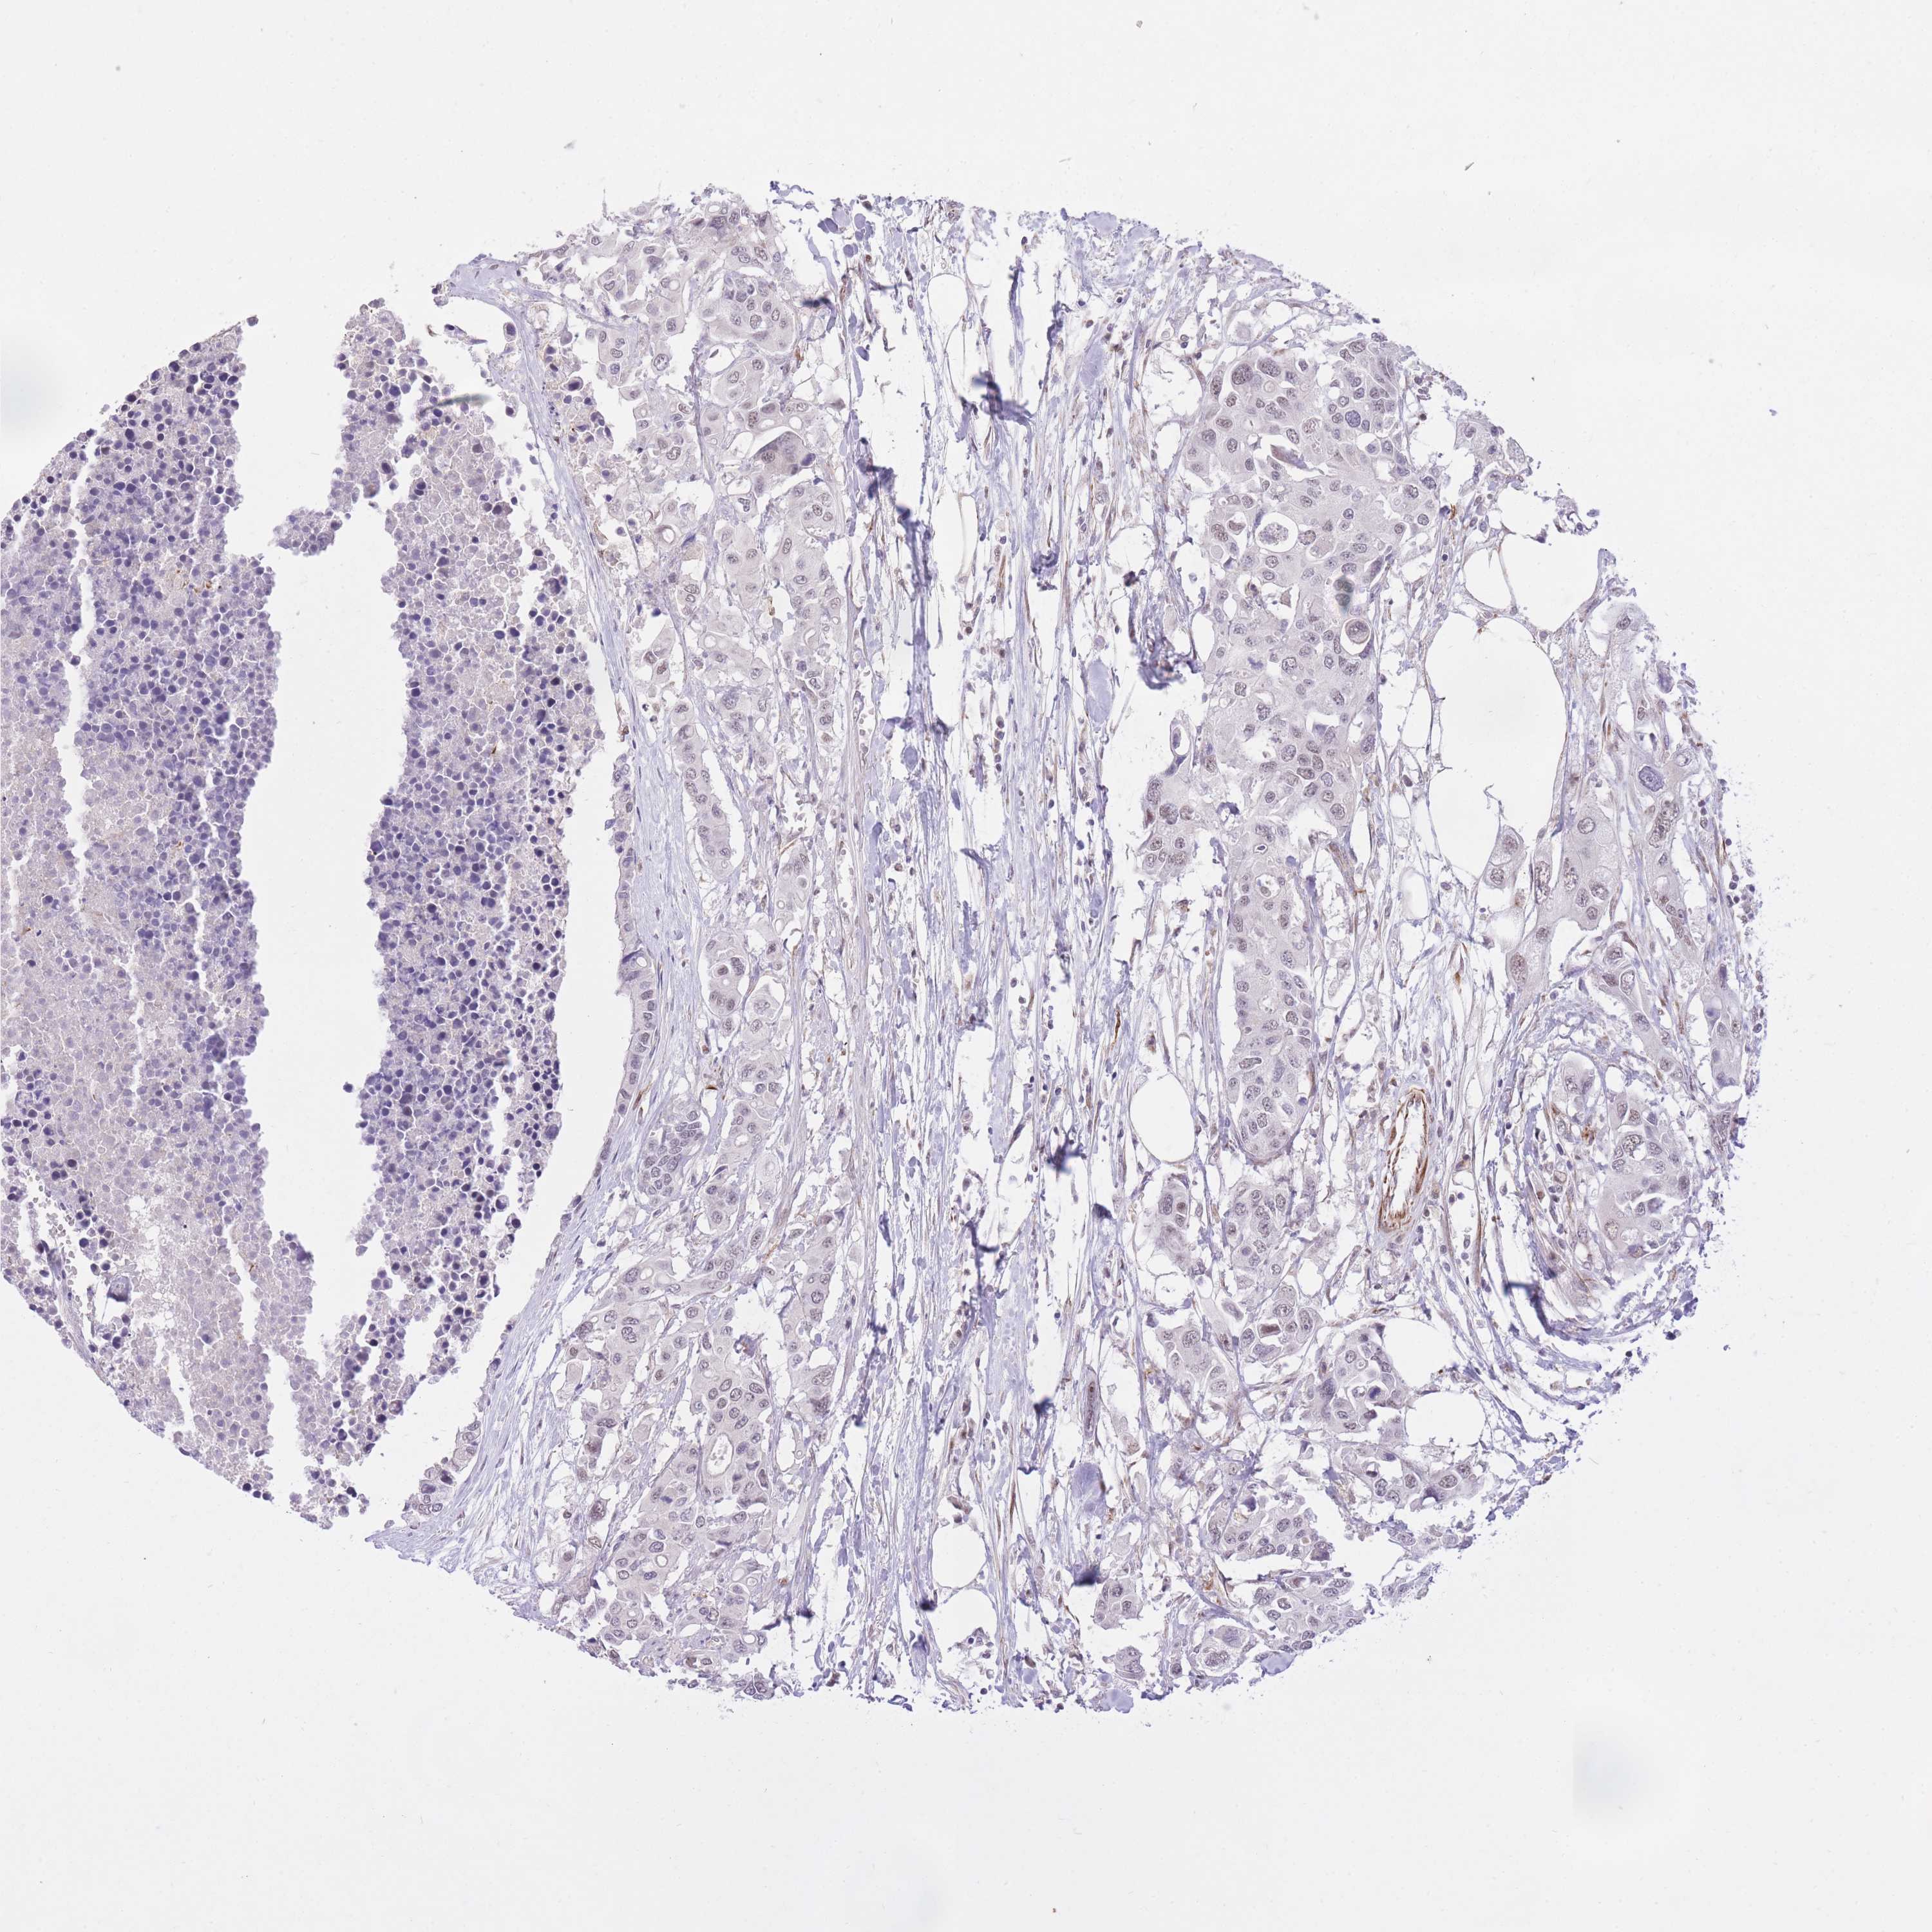

CANCER COLORECTAL CANCER Show tissue menu

Colorectal cancer

Human cancer

Colon adenocarcinoma

Rectum adenocarcinoma